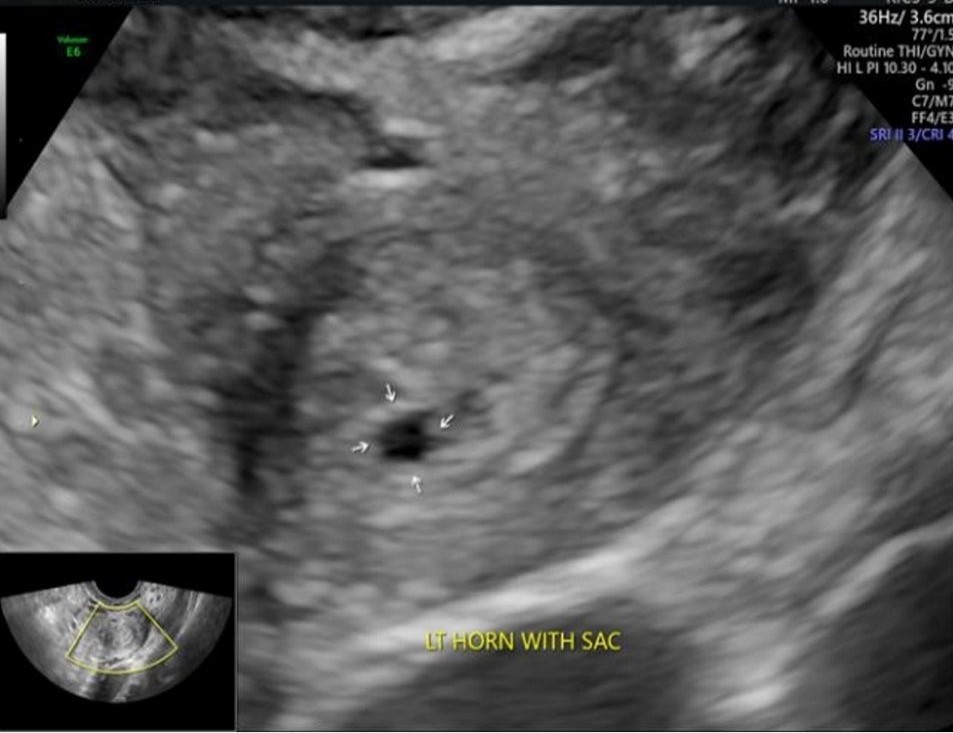

A 34-year-old G2P1 presented with 1 1/2 months of amenorrhea without pain or bleeding. Her history included an uncomplicated term vaginal delivery, laparoscopic detorsion of a twisted dermoid cyst (struma ovarii) ten years earlier, and a hysteroscopic metroplasty five years prior. Initial transvaginal ultrasonography did not reveal an intrauterine gestational sac, and she was classified as having a pregnancy of unknown location at four weeks and four days pregnancy. Serial β-hCG values rose from 53 to 2357 mIU/mL over ten days, but with irregular increments ranging from 11% to 76%, prompting concern for an ectopic pregnancy. Repeat transvaginal imaging demonstrated a unicornuate uterus with a separate left rudimentary horn containing a 1.8-mm gestational sac the left ovary showed a corpus luteum and both ovaries had polycystic morphology (Figure 1).